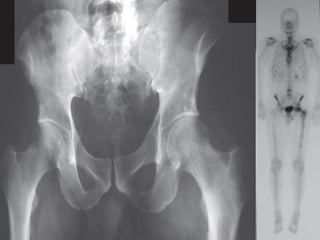

 A.K.A “Enostoses”

 Benign lesions of cancellous bone

 Common in adults, sites – Pelvis, femur

 Usually asymptomatic

 Imaging studies - Small round area of

increased density in cancellous bone with

radiating spicules at periphery.